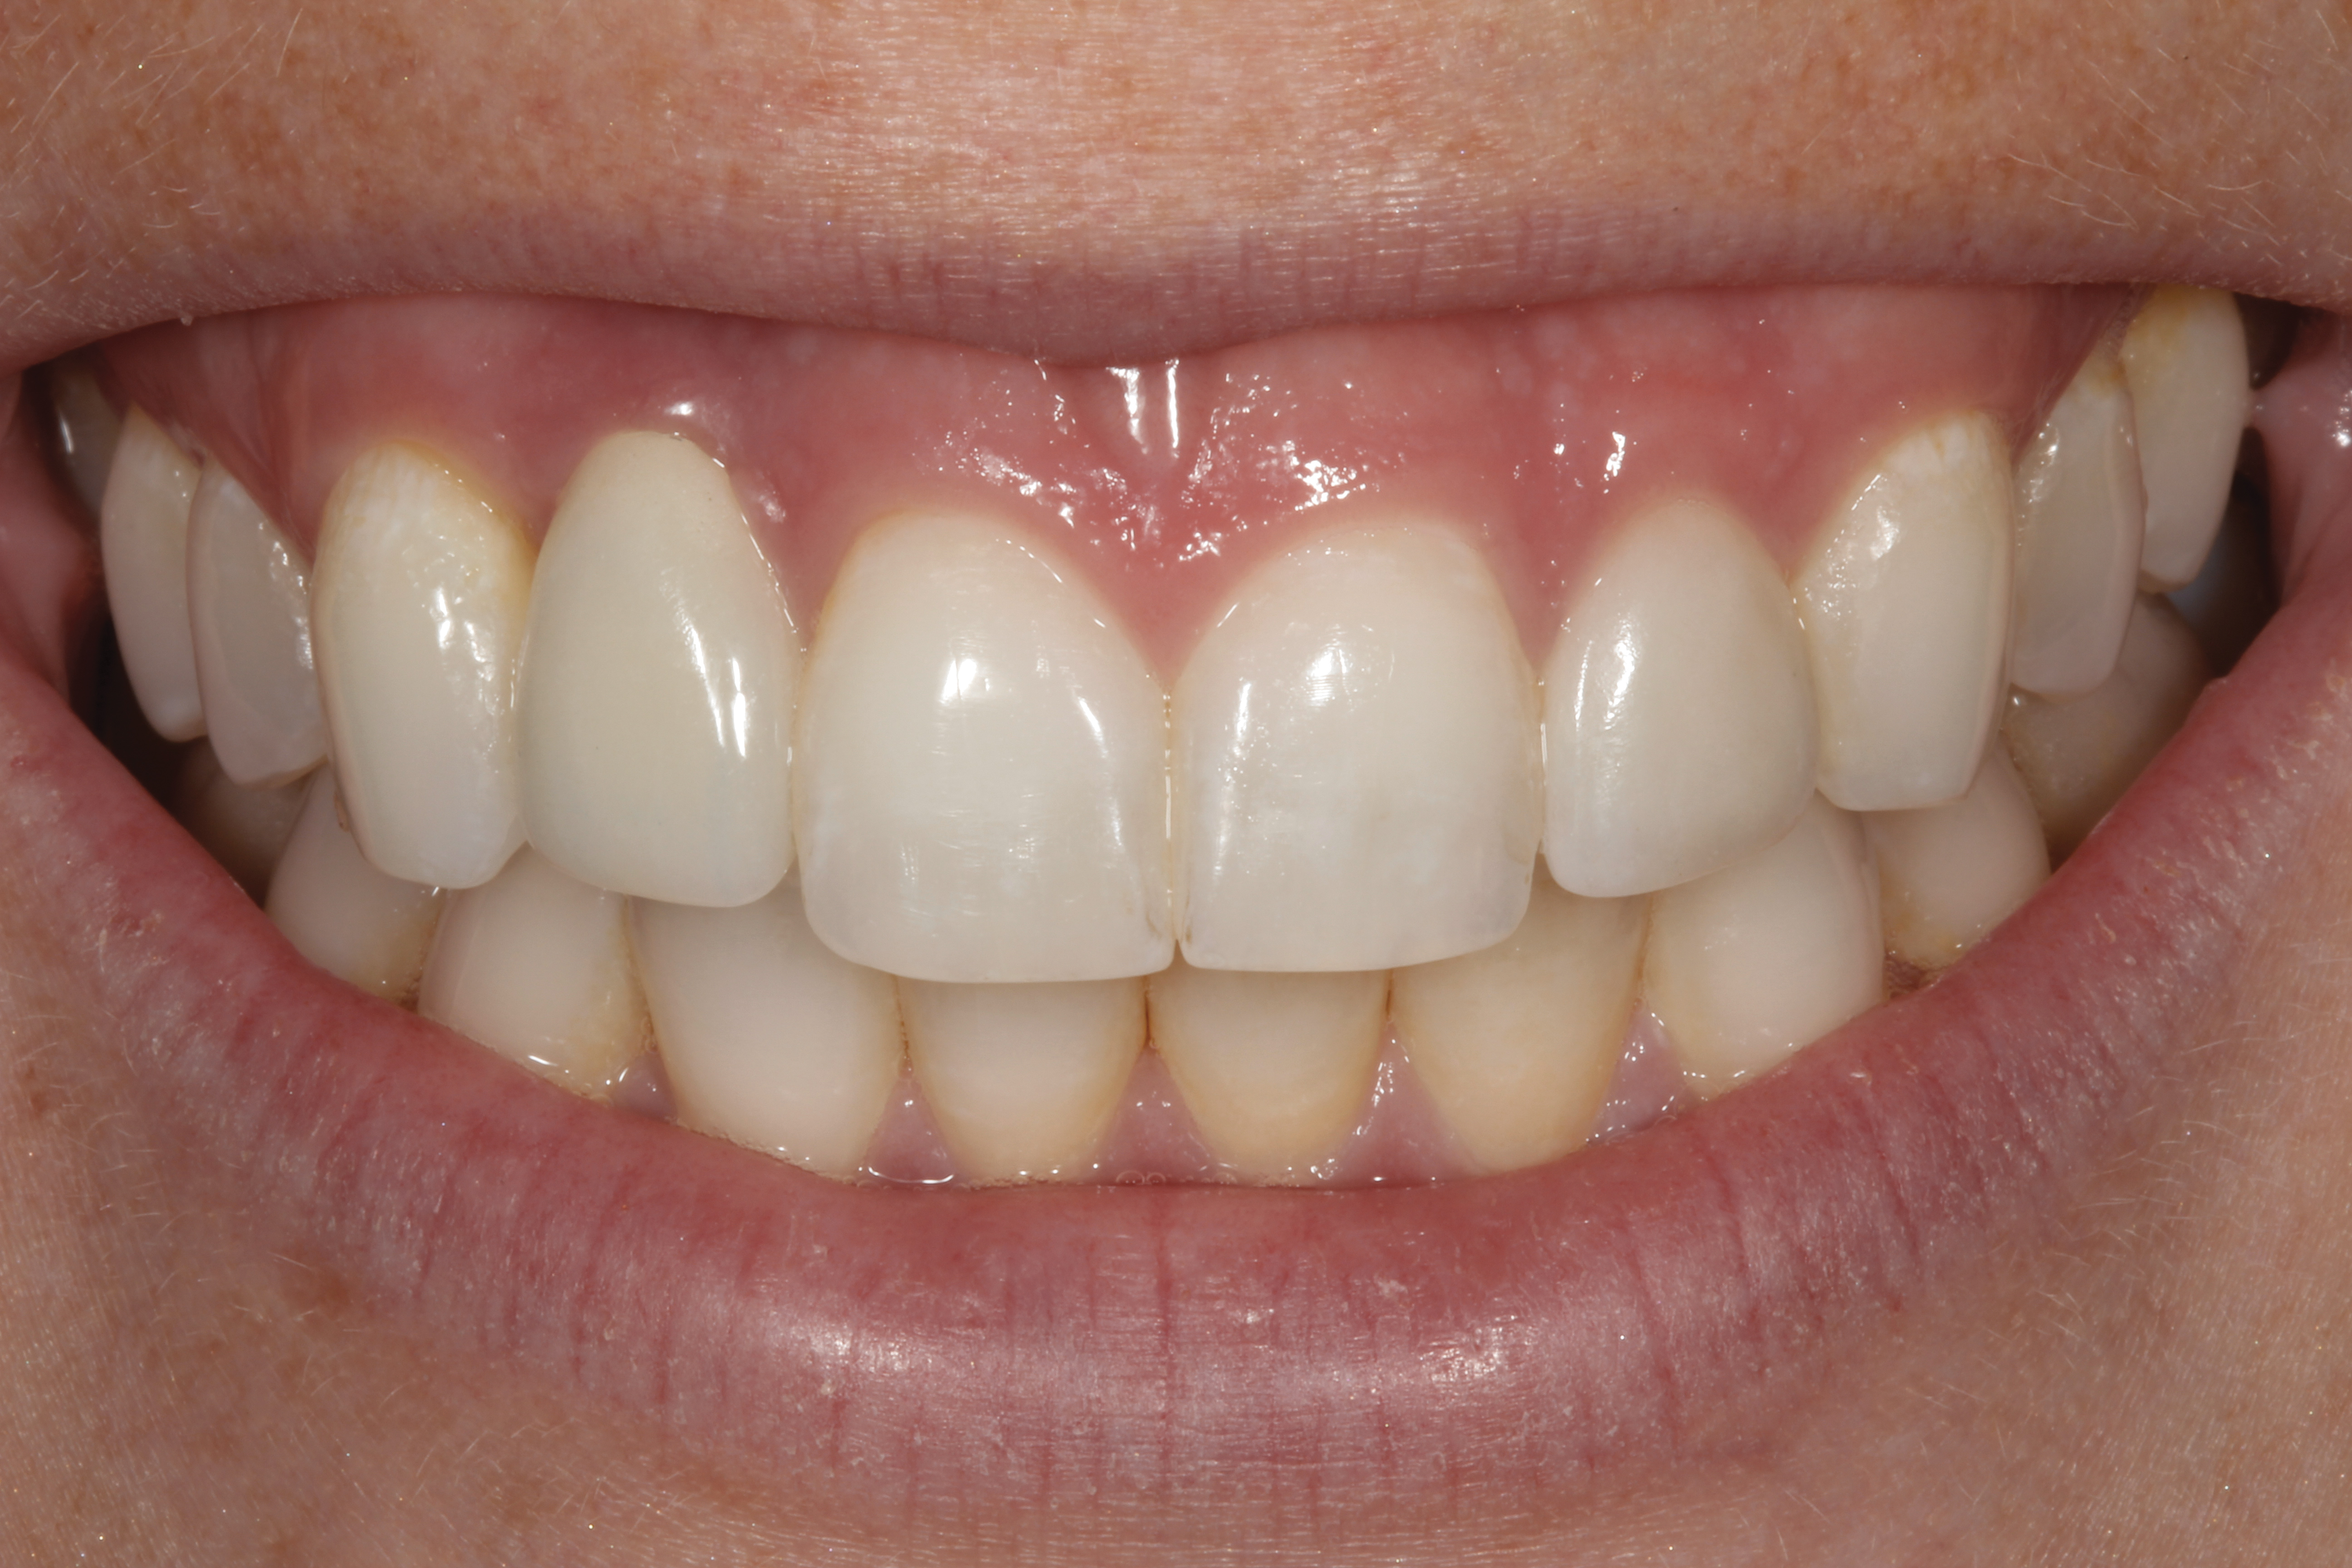

Fig 14. The extraoral smile view of the esthetically satisfied patient at 4 years recall.

Figure 14

Fig 45. The definitive crown tooth No. 26 seated in place and provisionally cemented. The recession defect was eliminated with the removal and replacement of a new implant in the proper position.

Figure 45